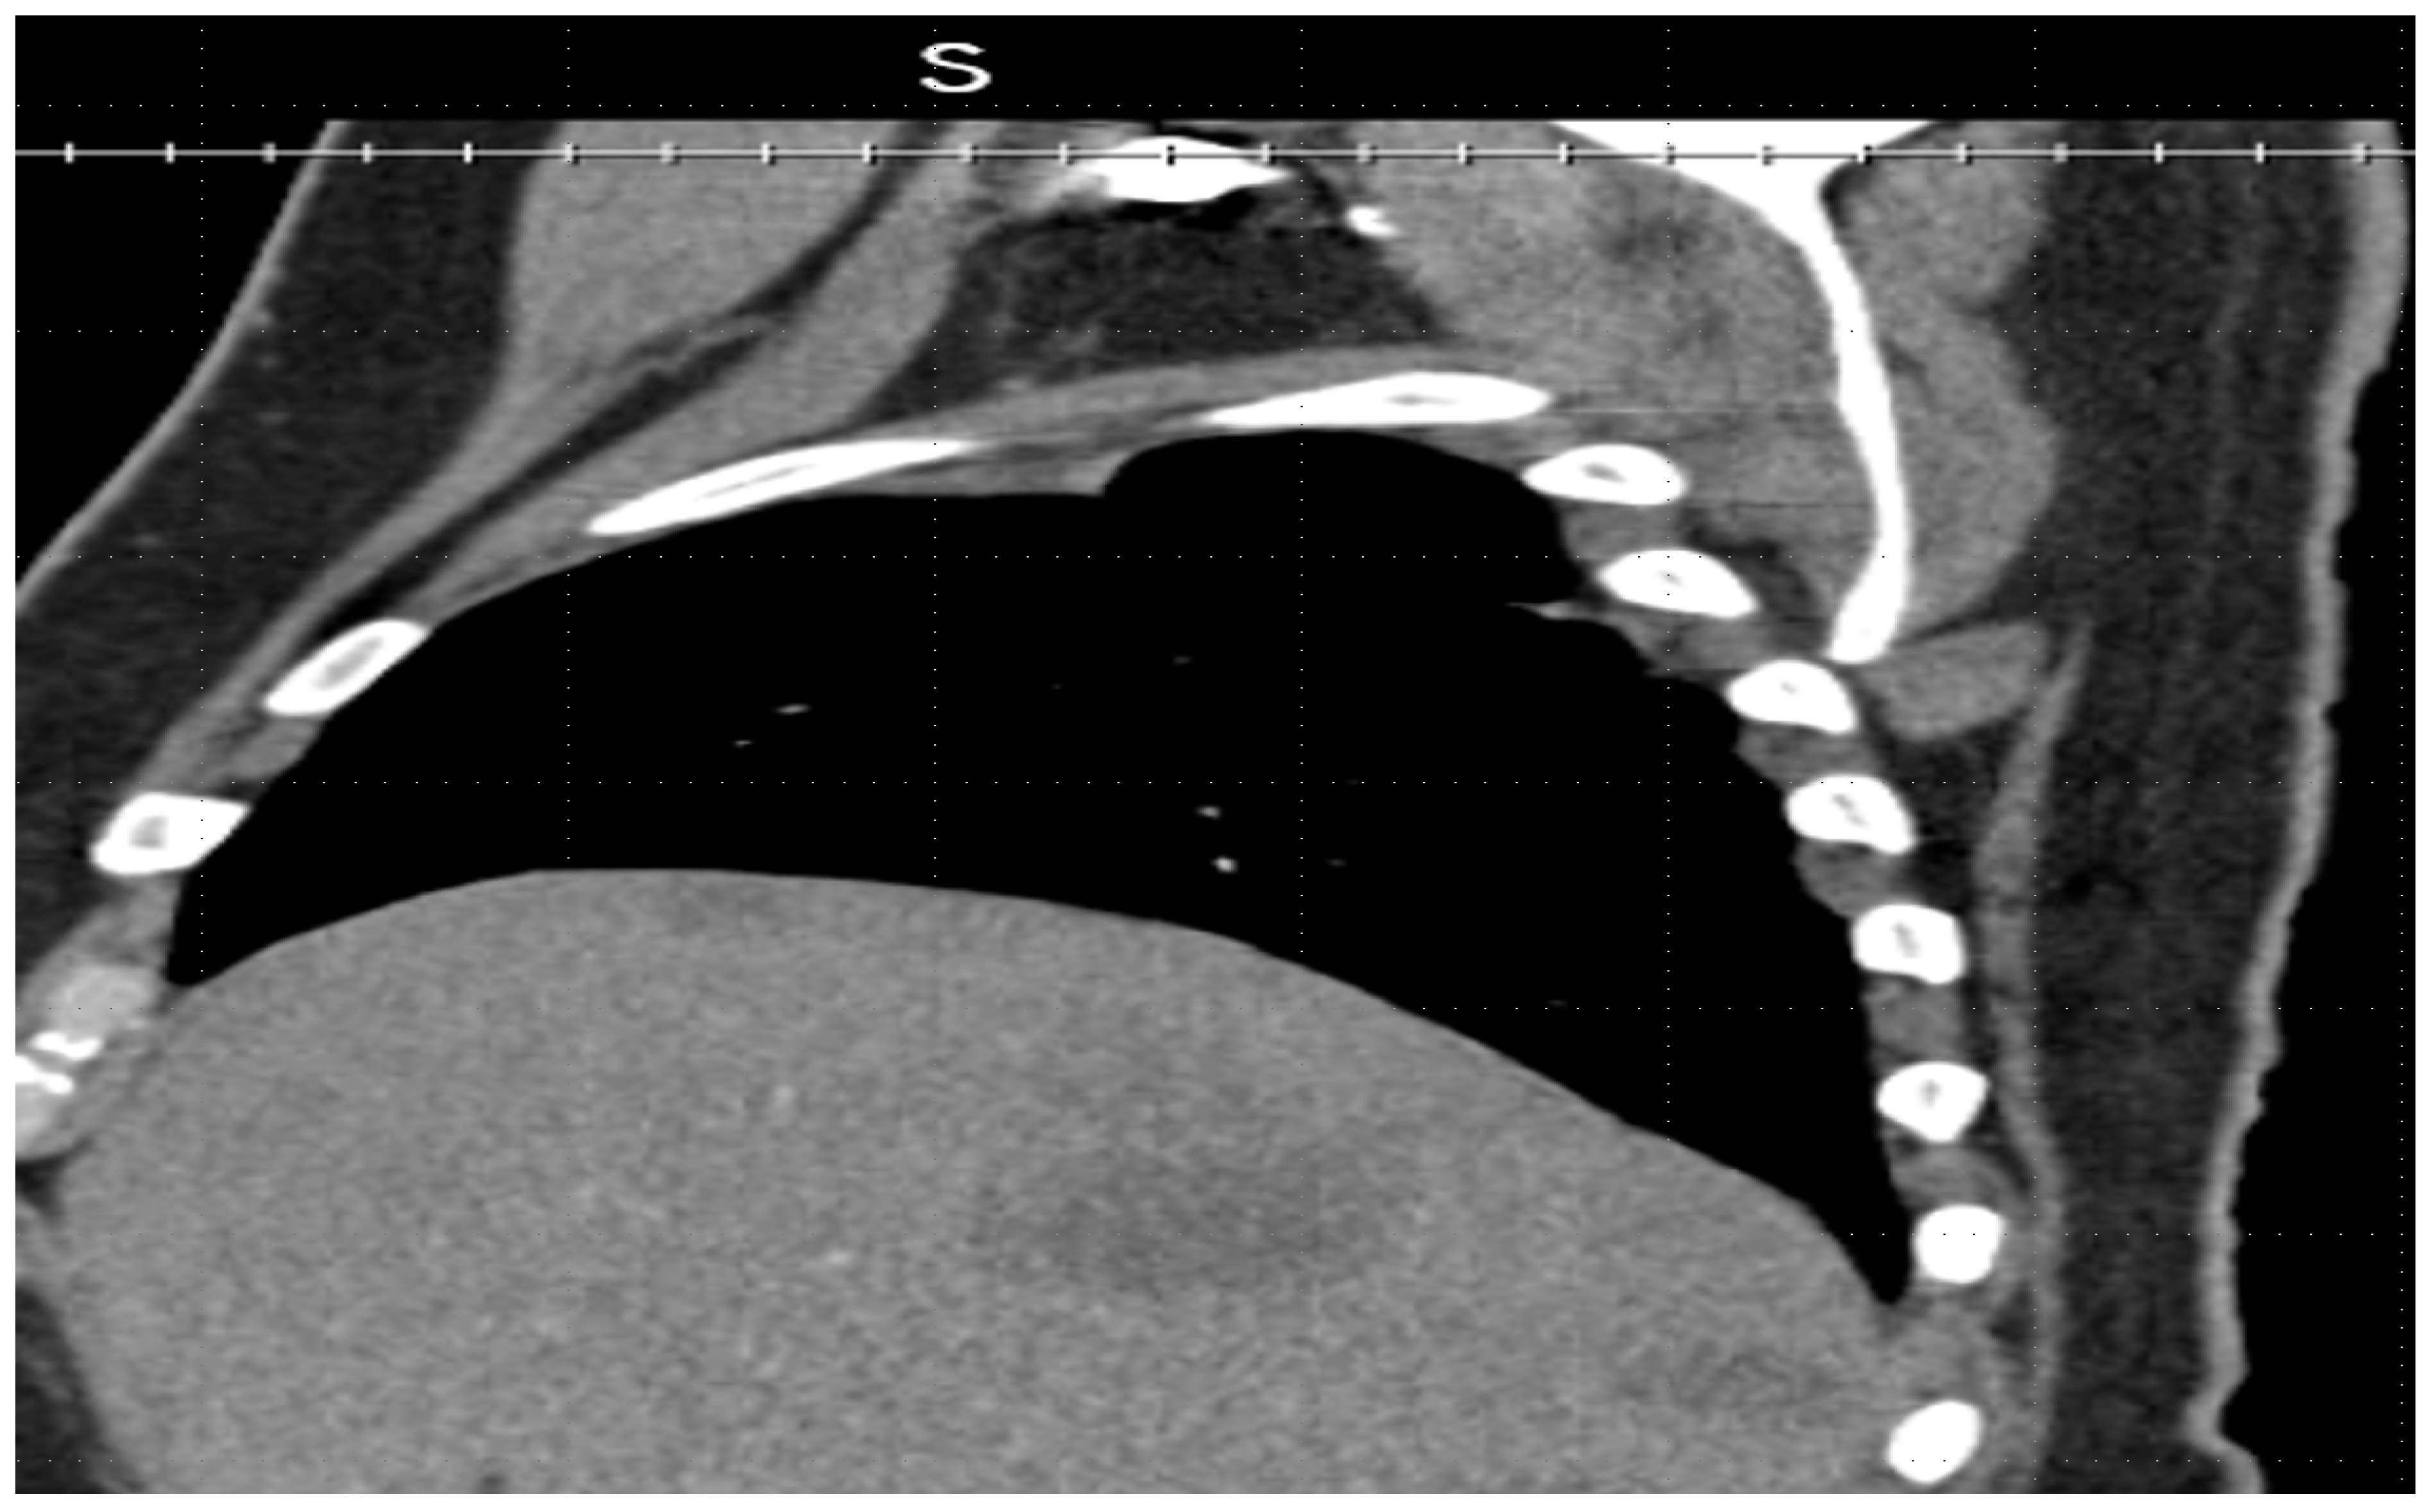

Imaging revealed multiple new hepatic lesions (Figure 2 and Figure 3), bilateral pulmonary nodules, and a new 2.9-cm left adrenal nodule, favoring a diagnosis of a metastatic tumor. The patient was admitted to the hospital for a higher level of care.

Figure 2.

Sagittal Computed tomography imaging revealed multiple new hepatic lesions.